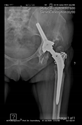

The radiological examination allowed us to verify the close bone-to-implant contact and the unchanged position of the implant during follow-up.

In all the cases operated with the above-described targeting procedure, the stems of the cups remained between the cortical bone surfaces without perforation of the linea terminalis, as shown by postoperative radiographs. There were no complicated surgical situations. In 16 cases, the wound healings were uneventful, and the hips were able to bear weight again after postoperative rehabilitation.